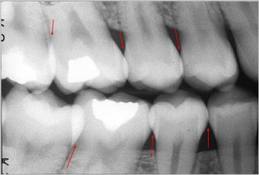

Si las radiografías están disponibles, el

primer paso es clasificar las lesiones de caries coronal en

dientes posteriores de acuerdo con los grados que están en

la Tabla 4.

Sistema radiográfico ICDAS

(Radiografía Bite-Wing) |

Sano |

R0 |

No hay

radiolucidez |

Estadios

iniciales * |

RA1 |

Radiolucidez en

1/2 externa del esmalte |

RA2 |

Radiolucidez

en la 1/2 interna del esmalte ± UAD

(Unión amelo-dentinaria) |

Se lo considera aún un estadio

inicial porque no hay dentina

infectada ) |

RA3 |

limitada al 1/3 externo de la

dentina |

Estadio

moderado

(En este estadió

comiemza la infección de la dentina por bacterias orales) |

RB4 |

Radiolucidez que

alcanza hasta el 1/3 medio de la

severos

(Infección franca de la dentina) |

RC5 |

alcanza hasta el 1/3 interno de la

dentina, clínicamente cavitada

RC6 |

la pulpa, clínicamente cavitada

|

Tabla 4: Clasificación

radiográfica ICDAS